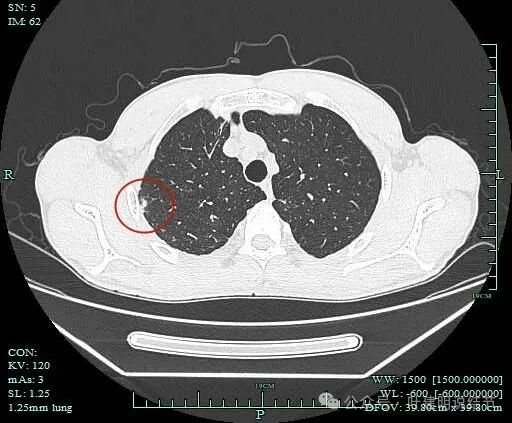

右上病灶1:

影像截图:

病灶出现,密度较高,不是圆形或类圆形,边缘略模糊。